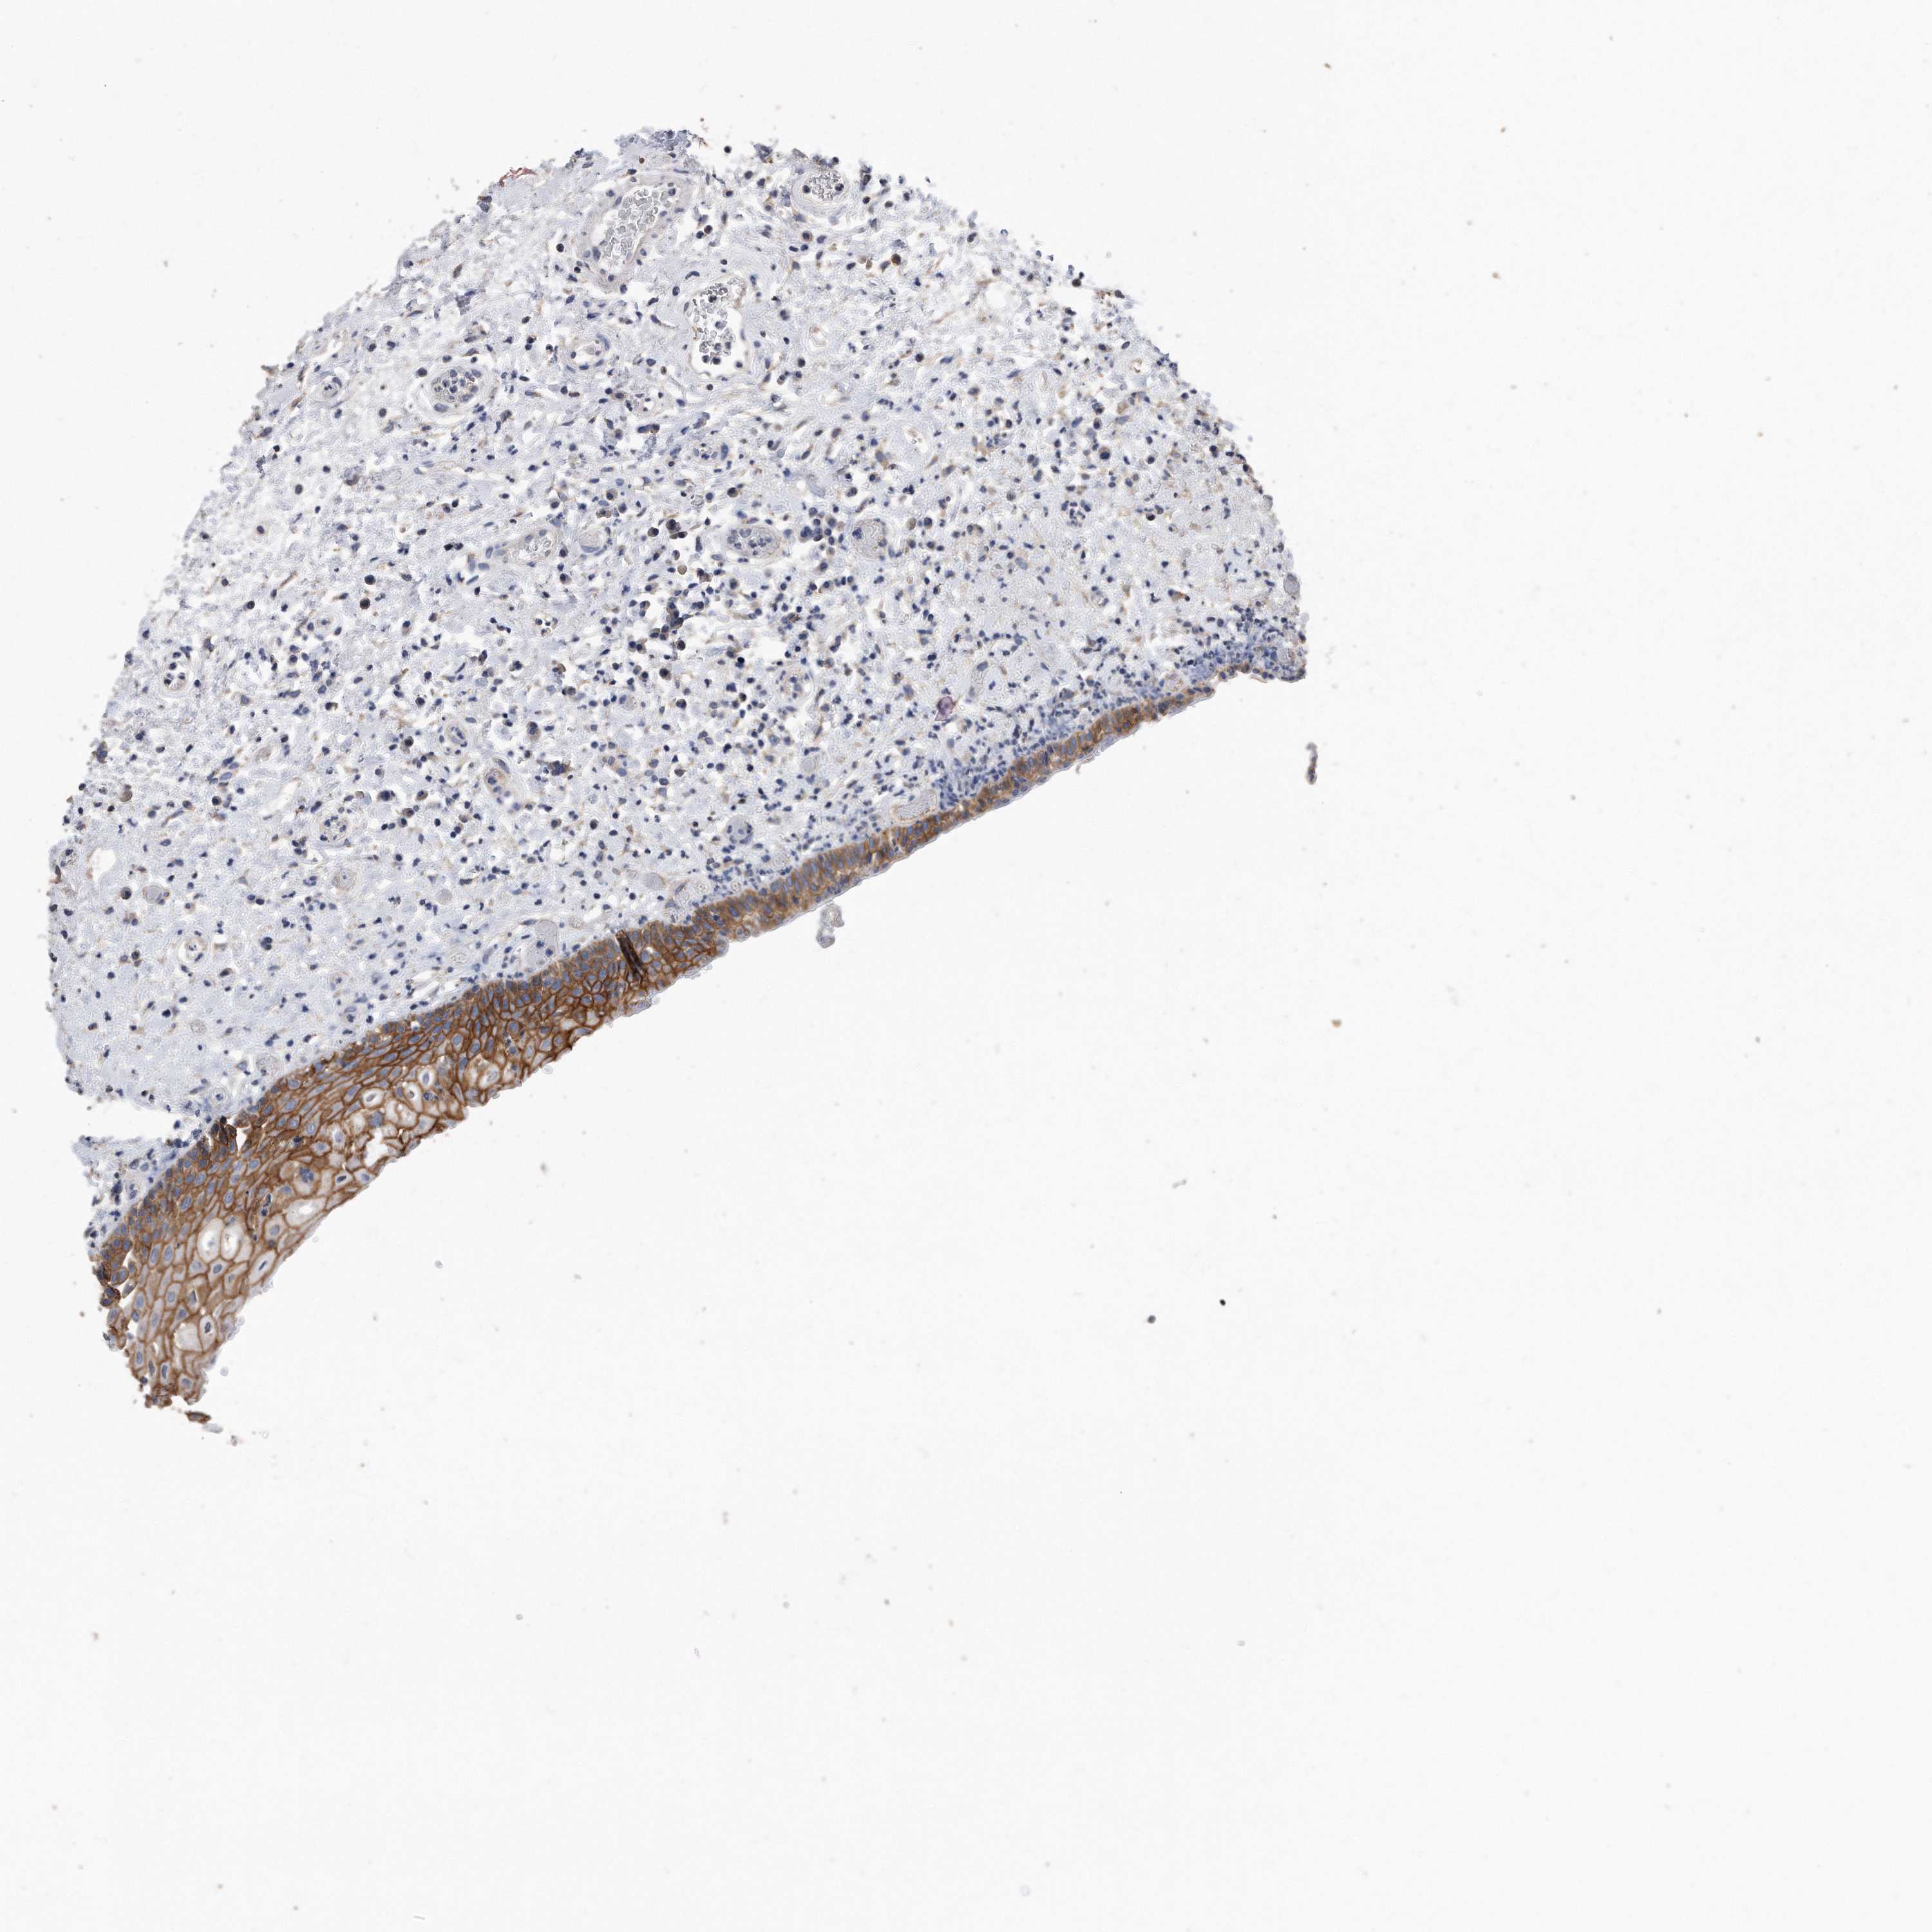

CDCP1